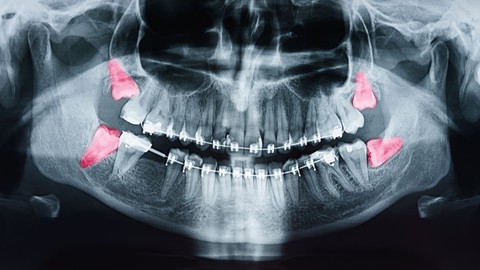

Nạn nhân của vụ việc này là Yuta Tomikawa, lúc đó mới 17 tuổi và đang là học sinh lớp 12. Cậu bé đã đến phòng khám để nhổ hai chiếc răng khôn nhưng không ngờ lại thiệt mạng.

Phòng khám nha khoa tại Sakai, được vận hành bởi Hội Nha Khoa Sakai từ năm 2008, là cơ sở chuyên phục vụ cho những bệnh nhân gặp khó khăn khi điều trị tại các phòng khám nha khoa thông thường. Gia đình của Tomikawa cho biết, cậu bé có rối loạn phát triển và đã đến phòng khám để tiến hành nhổ răng dưới sự giám sát của đội ngũ y bác sĩ chuyên nghiệp.

Theo thông tin từ cảnh sát tỉnh, vào khoảng 1 giờ chiều ngày 13 tháng 7, nữ bác sĩ 34 tuổi đã gây mê cho Tomikawa và đặt ống oxy qua mũi xuống khí quản. Tuy nhiên, cô bị cáo buộc không thực hiện các biện pháp cần thiết như việc đặt lại ống thở mặc dù có báo động từ thiết bị giám sát hô hấp của Tomikawa. Ngay cả khi đã nhận thức được tình trạng bất thường của bệnh nhân, giám đốc nam tuổi 55 của phòng khám, người cũng là một bác sĩ gây mê lại chậm trễ trong việc gọi dịch vụ cấp cứu.

Khi Tomikawa xuất hiện triệu chứng bất thường, bác sĩ tin rằng đó là do co thắt phế quản và đã tiêm thuốc nhưng không có cải thiện. Khoảng 2 giờ 25 phút chiều, họ mới gọi xe cứu thương khi cậu đã ngừng tim. Một nguồn tin tiết lộ rằng, mức độ bão hòa oxy trong máu của Tomikawa, thông thường sẽ là 96% hoặc cao hơn, đã giảm xuống còn khoảng 20%. Cậu bé đã không thể giành lại sự sống và qua đời vào ngày 9 tháng 8 tại bệnh viện sau khoảng một tháng. Nguyên nhân cái chết được xác định là do thiếu oxy não cục bộ.

Cảnh sát tỉnh Osaka đã kết luận rằng, dù ống oxy được đặt đúng vị trí ban đầu, nhưng sau đó đầu ống đã bị tách ra khỏi khí quản do nguyên nhân không thể xác định. Sau khi nghe ý kiến từ khoảng 40 nha sĩ, cảnh sát tin rằng nếu các biện pháp phù hợp được thực hiện, Tomikawa có thể đã được cứu.